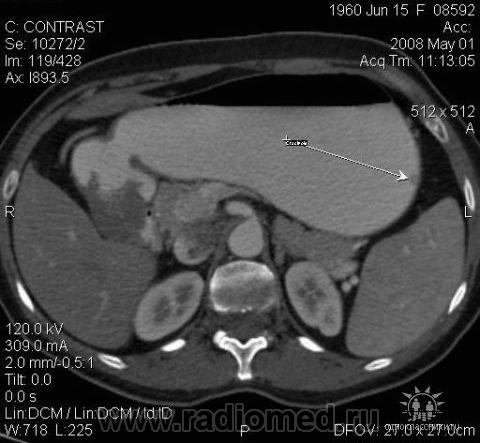

3.Лимфома желудка (MALT Lymphoma). Обратите внимание, экзофитного компонента нет, такие лимфомы растут интра-мурально. Диагноз верифицирован морфологически. (собственное наблюдение).

4.Рак желудка. Аналогичные наблюдения я уже демонстрировал ранее. В настоящее время, таких пациентов не оперируют без предварительной КТ визуализации, которая позволяет провести стадирование процесса и адекватное планирование объёма оперативного вмешательства. (собственное наблюдение).

Желудок растянули уже дополнительно; я стандартно даю на столе выпивать 2-3 стакана контраста сразу перед исследованием; этого в большинстве случаев достаточно. У данной пациентки, на изначальных сканах (к сожалению я их не сохранил, давно было дело), возникло подозрение на локальное утолщение стенки, поэтому дал выпить на столе дополнительно ещё контраст, потом сделал контрольные сканы с хорошо растянутым желудком. Эндоскопия с удалением карциноидов была уже после КТ. Кстати, жалобы пациентки не были связаны с патологией желудка; это как бы "случайная находка". По поводу заключения, насколько я помню, я написал экзофитные опухоли желудка, карциноиды были перечислены в диф. ряду, наряду с полипами и метастазами меланомы.

С Раком желудка картина ясная: когда он большой, да ещё и экзофитный — лёгкая добыча рентгенолога. Но вы, конечно, можете видеть прямые признаки прорастания в соседние органы и метастазирования

Интрамурально растущая Лимфома желудка, наоборот рентгенологическим методом выявить очень проблематично (тем более в обл. свода желудка). И эндоскопия здесь не поможет.